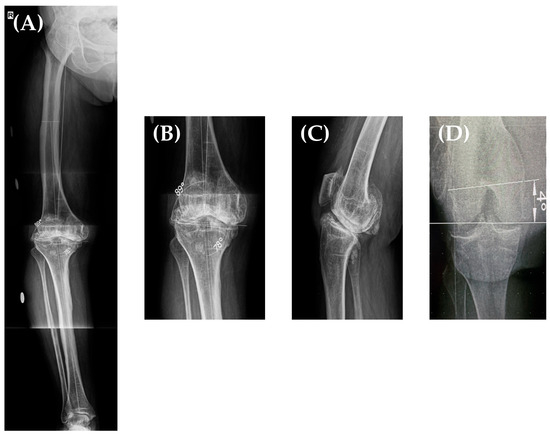

Taking all of this into account, we decided to perform a total knee arthroplasty on her right knee. Her preoperative planning long leg X-ray (Figure 3A,B) showed a grade II varus deformity of 12° (Hip-Knee-Angle—HKA of 168°), a lateral distal femoral angle (LDFA) of 89°, and a medial proximal tibial angle (MPTA) of 78° [13] with an increased posterior tibial slope and an IM angle (the angle between the femoral anatomical and mechanical axis) of 6°. Furthermore, in our clinic, we routinely perform a “seated view” X-ray which, according to our previous studies [14], helps in determining the distal femoral torsion. Using this special X-ray, where the patient sits on a radiolucent support with the knee flexed at 90°, we determine the posterior condyle angle (PCA) (and thus, the distal femoral rotation) by measuring the angle between the femoral trans-epicondylar axis (a line from the lateral epicondyle connecting it to the sulcus of the medial epicondyle) and the line connecting the posterior femoral condyles (Figure 3D); in this case, the femoral torsion was determined to be 4°.

Figure 3. Long leg X-ray of the patient’s right lower limb showing a HKA = 168°, LDFA = 89°, MPTA = 78° (A,B). Sagittal X-ray (performed at 30° of knee flexion)—increased tibial slope (C). Seated view X-ray showing a PCA (femoral torsion) of 4° (D).